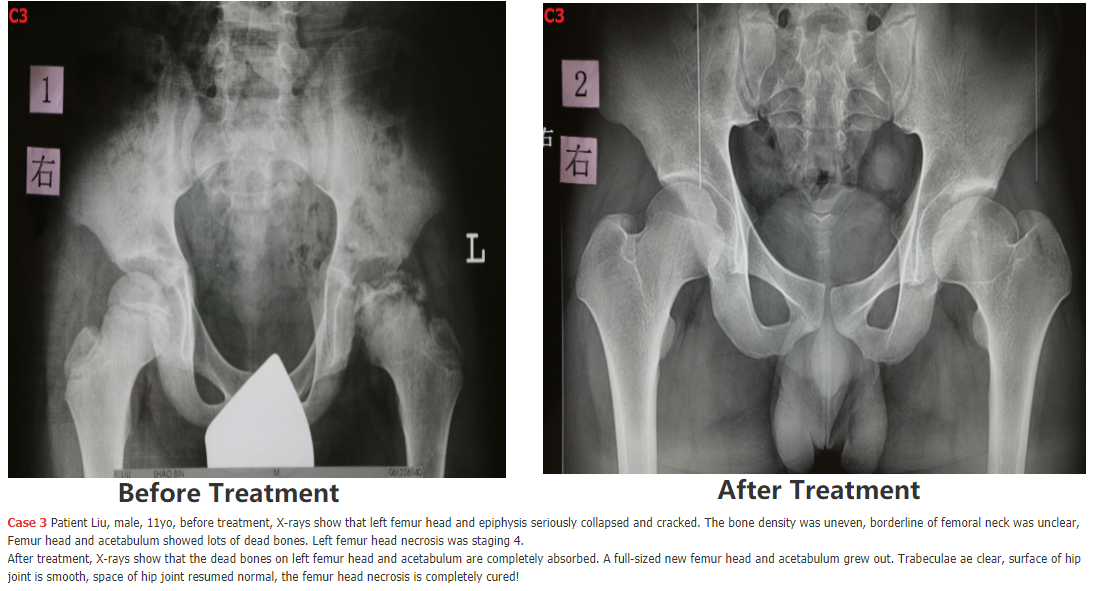

5. following are SOME Chinese patients we have cured - we will add the cases 5, 6, 7, 8, 9, 10, 11, 12.... SOON